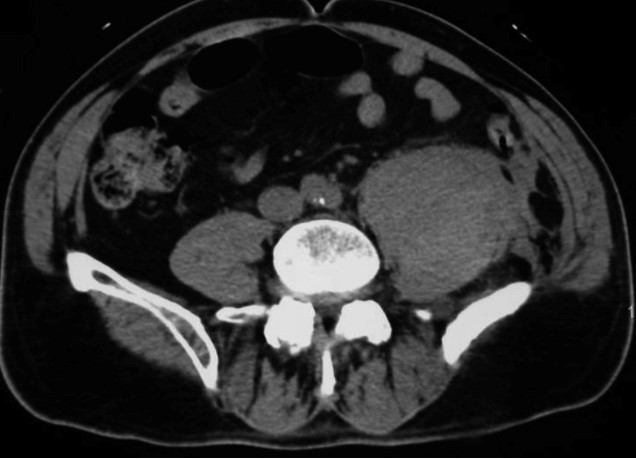

Tableau de déglobulisation + cruralgie L4 (douleur de la face antérieure de la cuisse gauche) et douleur de la fosse iliaque gauche.

Il faut éliminer un hématome profond et notamment un hématome du psoas.

Vous retrouvez effectivement un hématome du psoas avec un blush au temps artériel. La patiente est tachycarde et hypotendue.

Voici le scanner :

Tableau de choc hémorragique sur un hématome spontané du psoas à gauche chez un patient sous anticoagulant oral direct (AOD).

PPSB = complexe prothrombinique : Octaplex, par exemple (500 UI/20 mL, 25 UI/kg) –> 80 kg : 40 mL

– traitement de la cause :

ici blush au temps artériel sur le scanner –> radio-embolisation